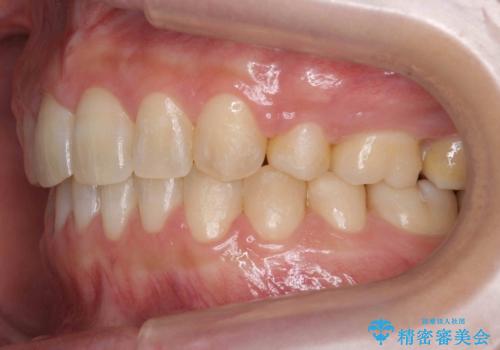

- 前歯のすきまを気にして来院。

奥歯が1歯対1歯で、過蓋咬合を呈していました。

short faceであり、結果上顎の臼歯を近心に大きくロスさせることになったたため、非常に長く治療期間はかかりました。